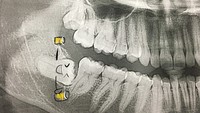

Rontgen gigi bungsu seorang wanita yang mengalami impaksi. Sepertinya sang gigi pesta terlalu liar sampai-sampai tak bisa lagi bangun tegak. (Foto: Instagram/stephanieelynnstudios)